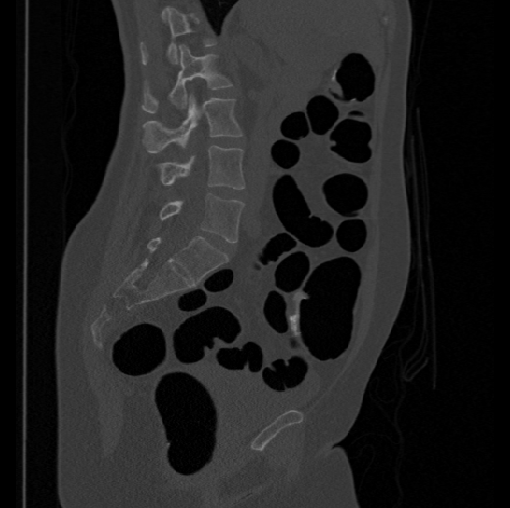

Spinal imaging via computed tomography (CT), magnetic resonance imaging (MRI), radiography, ultrasound, positron emission tomography (PET), and other radiologic imaging modalities is essential for noninvasively visualizing and assessing spinal pathology. Computational methods support and enhance a physician’s ability to utilize these imaging techniques for diagnosis, noninvasive treatment, and intervention in clinical practice. Analysis algorithms developed in the field of computer vision, computer graphics, signal processing, and machine learning have been adapted to analyze spinal images (Li et al., 2015). Conventionally, CT is preferred to study the spine due to a high bone-soft tissue contrast. There are diverse image appearance variations due to differences in vertebral position, metal artifacts and spinal diseases, etc., challenging the analysis algorithms. Fig. 1 gives some examples of these various conditions.

Images

GT

Predictions

We calculate the two metrics of each vertebra, and the results are reported in Table 2. On the one hand, our experimental results are close to those reported in reference (Sekuboyina et al., 2020) with the same model (nnUnet), verifying the high quality of our annotations. On the other hand, Table 2 shows it is difficult to segment the diseased vertebrae (the DSC of L6 is almost 0). Specifically, the existence of L6 confuses the model, resulting in prediction dislocations (see the last row in Fig. 4). Thus, our labeled dataset, which contains many L6 cases, is very valuable for the diseased vertebrae segmentation (we have stated those cases that are hard for annotation in the readme.txt file). Table 2 illustrates that the model trained with our annotations can achieve good performance on our CTSpine1K dataset but a much worse performance on the VerSe Challenge datasets, which explains there is an obvious domain gap between our annotated dataset and the public dataset. We infer the reason is that the COlONOG dataset is based on an empty stomach and colon, confusing the deep learning model by the changes of air content in the abdomen (see Fig. 3). Therefore, our annotations are a good complement to the existing datasets.

3.2.2 Qualitative results.

Some visualization results are presented in Fig. 4, where we can observe that the baseline model can achieve excellent segmentation results. Nevertheless, some failed predictions occur when spinal diseases exist, especially sacral lumbarization and lumbar sacralization. Besides, the image’s resolution of Z direction is closely related to the results, and a lower resolution leads to worse results. Maintaining a reasonable performance for a low resolution is a research challenge. Image superresolution (Peng et al., 2020) might be worth exploring.